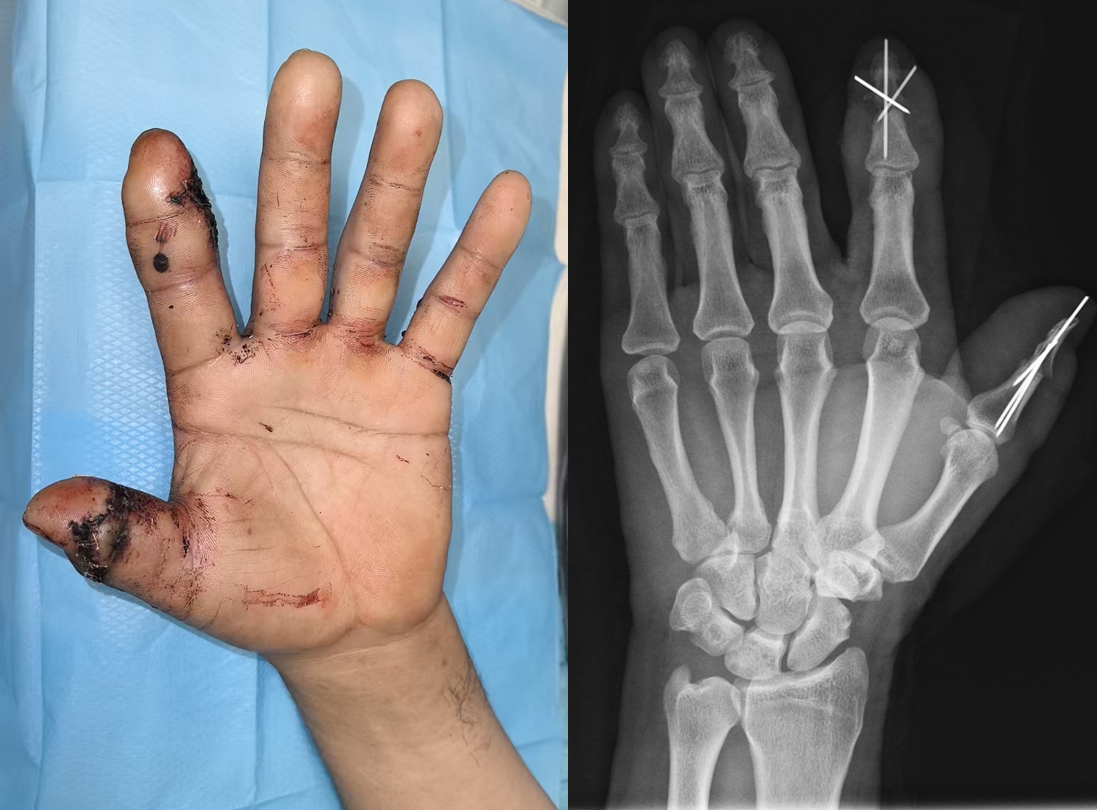

患者谢先生在工作时不慎被电锯误伤,导致左手拇指远节完全离断,同时合并食指背侧开放性骨折。院前急救人员使用清洁纱布妥善保存拇指断指并清理包扎伤口后,将谢先生送至我院急诊。考虑到断指再植的黄金时间为伤后6-8小时,骨科医疗小组在姜为民主任的指导下迅速有序地展开行动,有鉴于这是我院真正意义上的首例断指再植手术,为确保万无一失,我院骨科团队在积极完善术前准备、协调麻醉科手术室的同时,及时邀请到苏州瑞华医院王凯副主任医师断指再植专家协助手术,为再植手术的成功创造条件。

断指再植手术需要极其精细的操作,需在直径不足1.2mm的指动脉上完成端端吻合,并同时重建拇指的静脉回流及神经支配;食指背侧的皮肤缺损则通过精准转移带血管蒂皮瓣覆盖骨外露创面。苏大附四院骨科王亮副主任医师、潘明铭主治医师和王凯副主任医师密切合作,采用高倍显微镜下“血管神经束优先吻合”策略,术中探查发现高速电锯引起软组织挫伤严重,同时拇指动脉较细、动脉痉挛明显。医疗团队凭借精妙的显微外科技术,克服了手术中遇到的种种难题,实现动静脉通血“一次成功”。

患者术后左手形态基本恢复,拇指末梢血运良好,术后2周断指基本存活,复查X光片显示拇指及食指远节指间关节对合良好、形态基本恢复正常。